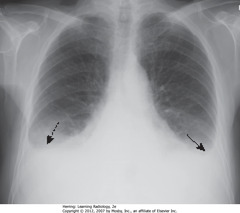

Pleural Effusion

An accumulation of an exudate or transudate in the pleural cavity. (Not in the lung itself, just the pleural cavity) Treatment: Because pleural effusion can compress the lung (can cause atelectasis) & cause collapse, it is important that the fluid be removed. If large amounts of fluid, a chest tube may be used. Antibiotics for infection.

What would you expect a chest x ray to look like for a pleural effusion?

costophrenic angles are blunted or totally lost because of fluid.

What type of radiographs should be taken to demonstrate a pleural effusion

Chest x-rays and a lateral decubitus chest. Doing a lateral decubitus helps differentiate from other respiratory diseases/pathologies.